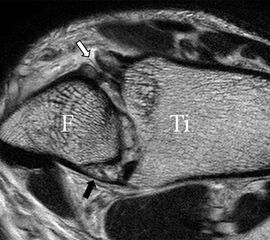

Jedoch findet man sich auch hier mit dem Problem der in den Standard-Projektionen schräg verlaufenden Syndesmose konfrontiert. Der oligofaszikuläre Aspekt der vorderen Syndesmose kann in der axialen Schnittebene eine zum Verwechseln ähnliche Morphologie wie eine Ruptur aufweisen (Abb. 15 b und c). Doppelangulierte Schnitte entlang der Achse (schräg koronar/schräg sagittal) lassen hingegen eine eindeutige Beurteilung der Bandstrukturen zu (Abb. 16) und verbessern die Syndesmosendiagnostik.

Bezogen auf die Transversalebene verläuft die Syndesmose ca. 30° schräg cranio-caudal anguliert (Abb. 15 a). Häufig lassen sich drei Hauptfaszikel differenzieren: das kürzeste superiore, das stärkste mittlere und das längste kaudale Faserbündel. Ein akzessorisches Bündel, das anteriore-inferiore, tibiofibulare Ligament (AITFL) oder auch Bassett-Ligament wird in 80-94% der Patienten nachgewiesen 8. Dies weist einen unmittelbaren Bezug zur anterolateralen Talusschulter auf (Abb. 17). In Kombination mit einer Außenbandinstabilität und konsekutivem, talarem Vorschub kann dieses zu einem Impingement an der anterolateralen Taluskante führen mit nachfolgender chondraler oder osteochondraler Läsion.